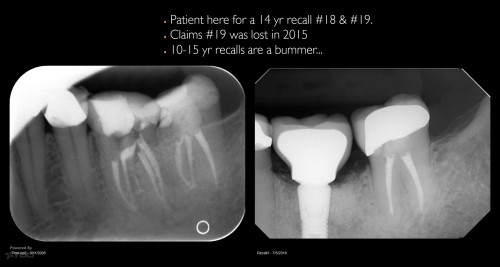

Disappointing recall

Busy recalling cases from the 10-15 yr time frame. Had I just done 5 yr recall, I’d never know …. gbc